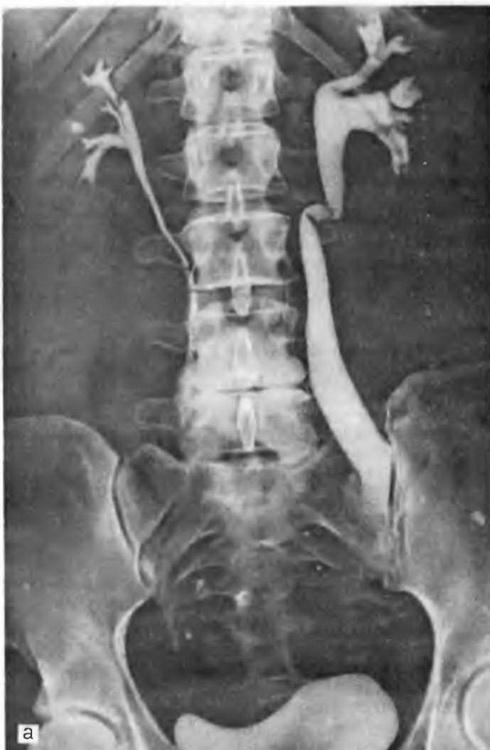

Ендометріоз сечоводів. Дана локалізація захворювання за своєю значимістю надзвичайно серйозна, оскільки може спричинити за собою стенозування сечоводу (рис. 15), розвиток гідро-уретера, гидропиелонефроза і втрату нирки.

При стенозірованіі нижнього відділу сечоводу ендометріозом по мірі розвитку патологічного процесу порушується перистальтика його; він розширюється і подовжується, виникають перегини його в різних відділах, в тому числі і у верхній третині. На урограмах може бути виявлено зовнішню схожість із змінами, описаними Остлингом. При рентгенологічному обстеженні апаратом з електронно-оптичним перетворювачем диференціювання не викликає труднощів з урахуванням сталості зображення при хворобі Остлинга і мінливості картини при наявності перешкоди до відтоку сечі в нижньому відділі сечоводу. Крім того, після усунення перешкоди до відтоку сечі хірургічним шляхом (уретеролиз, резекцію рубцево-зміненої непериста л ьтирующей частини сечоводу та/або неоуретероцистостомия) эктазия сечоводу і його перегини зазнають регресу.